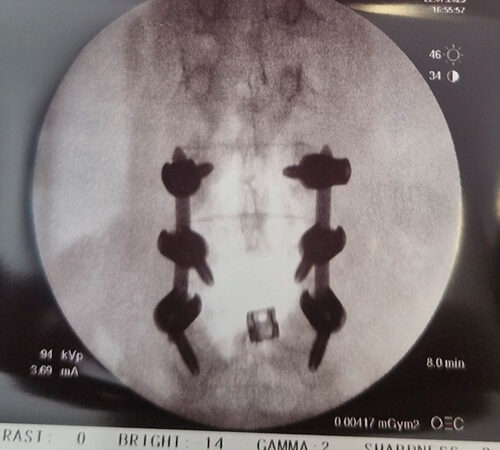

DIAGNOSI:

SPONDILOLISTESI CON STENOINSTABILITA’ L3-L5

Radiografia lombare pre-operatoria

Intervento chirurgico eseguito:

Artrodesi lombare mediante viti transpeducolari L3-L4-L5 + introduzione di cage intersomatica plif

Radiografia post-operatoria